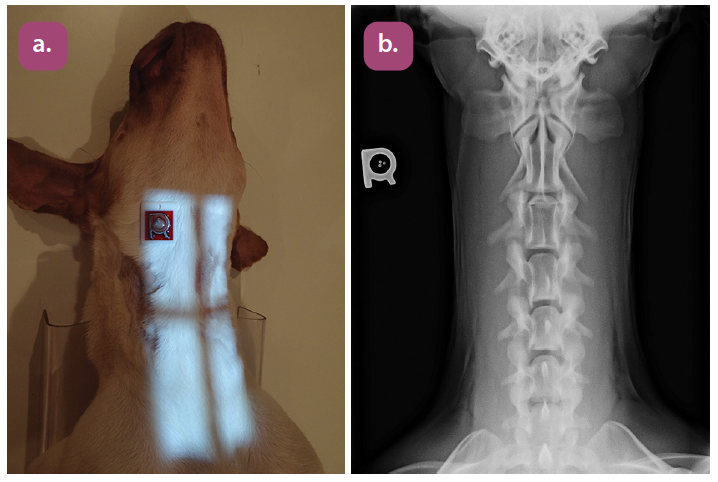

ventrodorsal cervical spine projection